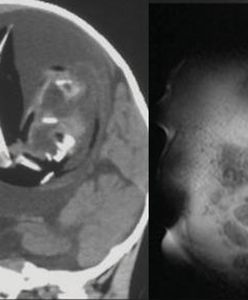

Lekarze przymocowali z powrotem głowę. 12-latek został potrącony na rowerze

12-letni Palestyńczyk Suleiman Hassan doznał wewnętrznego "ścięcia głowy" – podstawa czaszki i górna część kręgosłupa zostały oddzielone, ale skóra pozostała nienaruszona. Lekarze, żeby go uratować, przeprowadzili skomplikowaną operację.